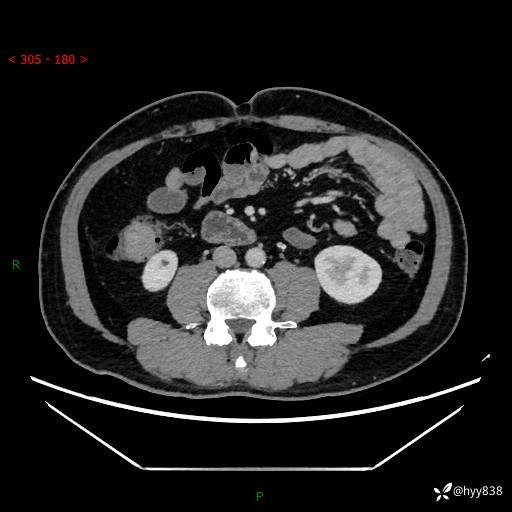

腹部CT增强扫描(外院CT平扫)

两期CT值:75hu 82hu